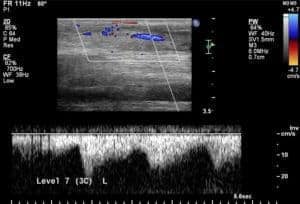

Doppler Ultrasonography for Monitoring Tendonitis in Horses

Colors displayed by Doppler ultrasonography could help vets better follow tendonitis’ healing processes.